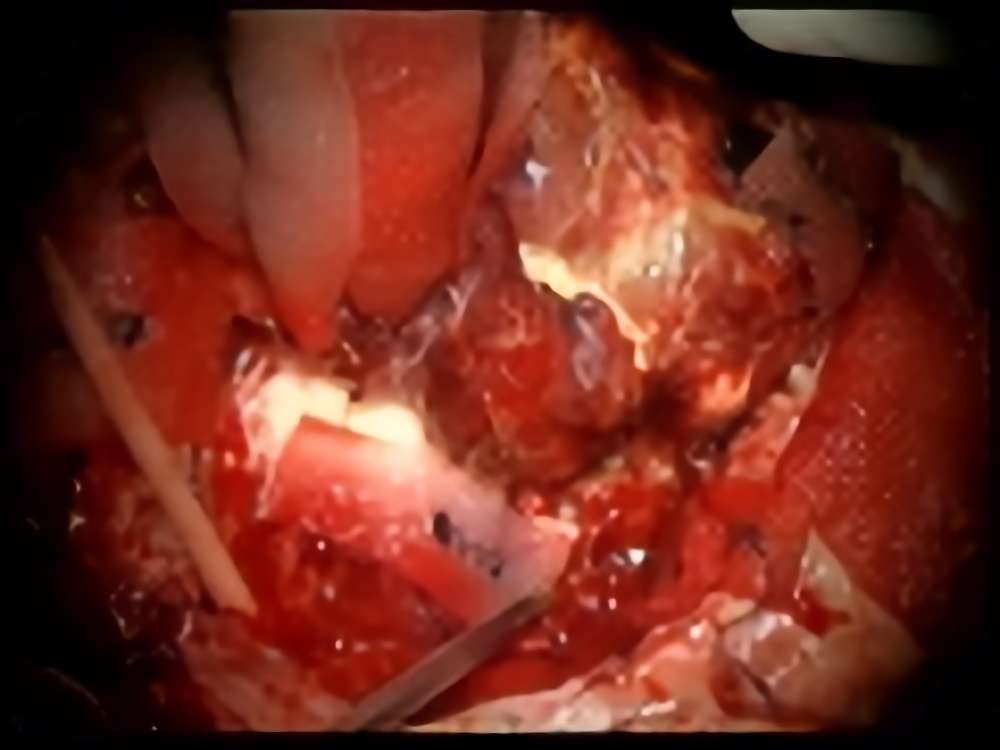

術中写真

摘出 前

摘出 中

摘出 後